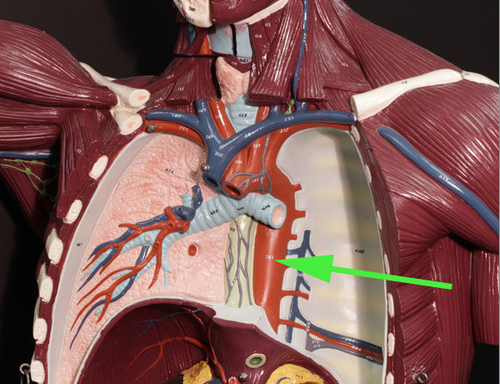

The vessel marked by the green arrow is a branch of a pulmonary artery

The vessel marked by the green arrow is a branch of a

pulmonary artery.

In the area marked by the green arrow, the aorta is called the thoracic aorta